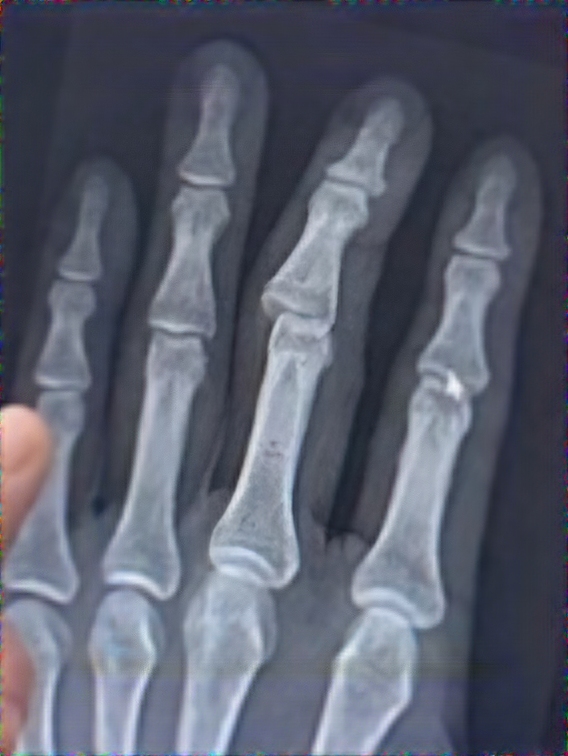

원래 사진은 좀 무서울 수 있어서 X-ray로 대체함 ㅜㅜ....공만보고 뛰던 중 턱을 발견하지 못하고 그대로 넘어졌으며 일어나보니 오른쪽 팔꿈치는 출혈과함께 찢어져 있었고 왼손가락 중지는 형체가 뒤틀려 있었다.